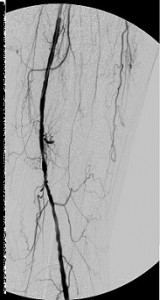

The images in the top panel illustrate multicentric moderate and severe (>50%) narrowings of the proximal left common femoral artery (LCFA) – not shown – and the superficial femoral artery and a focal critical stenosis of the proximal left tibioperoneal trunk in an elderly diabetic man with a chronic ulcer of his left foot. Notice that the critical tibioperoneal stenosis limits blood flow into the patient’s only named branch of his left popliteal artery, the peroneal artery, which is the principal path of blood inflow to the foot. Note, too, the severity of the lack of perfusion of the foot as shown by the “whiteness” of the patient’s hind foot.